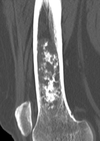

- Ground glass (BUZZWORD) lytic lesion with hazy matrix

Diagnosis?

This lesion is seen in the tibia and the jaw and it resembles FD with malignant potential

Adamantinoma Rx and Hx (histologically) resembles FD